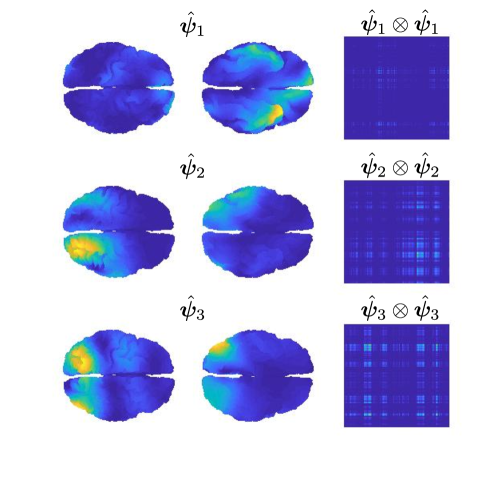

A regularization parameter common to all the PC components is chosen by inspecting the plot of the regularity of the first PC covariance functions () versus the residual norm, for different choices of the parameter. This is a version of the L-curve plot (Hansen, 2000) and is shown on the left panel of Figure B.2. Here we show the results for , in the appendices we show the results for . The energy maps of the estimated , and resulting from the analysis are shown in Figure 11. These are associated with the first three PC covariance functions , and . High intensity areas, in yellow, indicate which areas present high average interconnectivity, either by means of positive or negative correlation in time.

The second part of the analysis focuses on applying the proposed methodology to a multi-subject setting. Specifically, different subjects are considered. For each subject, the 6 minutes scan is used to compute a covariance matrix, resulting in covariance matrices . The template geometry in Figure 10 is used as a model of the brain space. Algorithm 2 is then applied to find the PC covariance functions on the template brain, associated with . We run the algorithm for iterations, and choose the regularizing parameter to be by inspecting the L-curve plot in the right panel of Figure B.2. The results for are shown in the appendices. The energy maps of the estimated functions , and and the associated first three covariance functions , and , are shown in Figure 13. High intensity areas, in yellow, indicate which areas present high average connectivity. In Figure 14, we show the subject-specific associated variances, both in the sensors space and the brain space.

The presented methodology opens up the possibility to understand population level variation in functional connectivity, and indeed, whether, just as we need different forward operators for individuals (due to anatomical differences), we should also be considering both population and subject-specific connectivity maps when analyzing connectivity networks. In fact, it is of interest to note that in both the single and multi-subject settings, the areas with high interconnectivity, displayed in yellow in Figure 11 and 13, seem to be at least partially overlapping with the brain’s default network (Buckner et al., 2008; Yeo et al., 2011). The brain’s default network consists of the brain regions known to have highly correlated hemodynamic activity (i.e. highest functional connectivity levels), and to be most active, when the subject is not performing any specific task. An image of the spatial configuration of the default network can be found, for instance, in Figure 2 of Buckner et al. (2008). From the plots of the associated variances in the sensors space (left panel of Figure 12 and Figure 14) we can see that these areas are also the ones that show high variability in connectivity across time or across subjects. This might suggest that the brain’s default network is also the brain region that shows among the highest levels of spontaneous variability in connectivity.